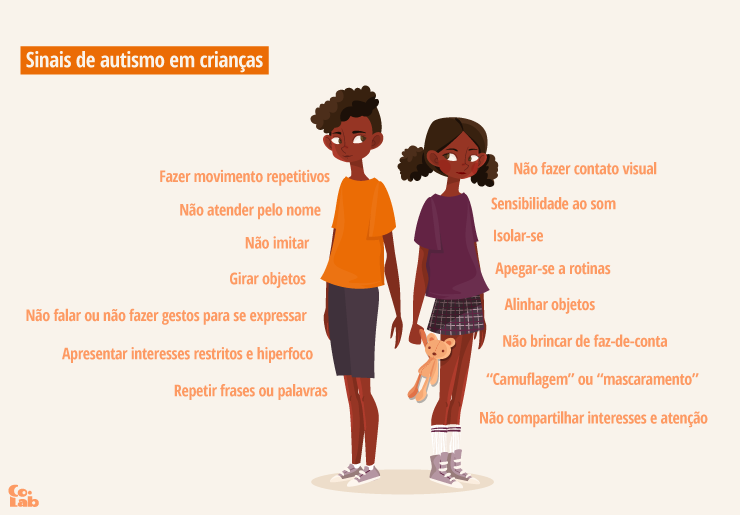

2 de abril: Dia Internacional da Conscientização do Autismo - Colab04 abril 2025

2 de abril: Dia Internacional da Conscientização do Autismo - Colab04 abril 2025